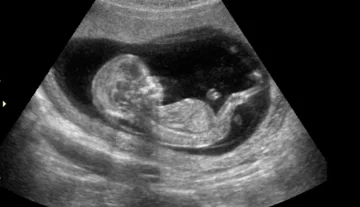

Un mujer se llevó una verdadera sorpresa en el momento en el que decidió hacerse una ecografía para ver la imagen de su bebé.

La joven de 36 años está embarazada de 7 meses y tomó la decisión de poder ver a su niño, para dar cuenta de que el embarazo transcurre con normalidad.